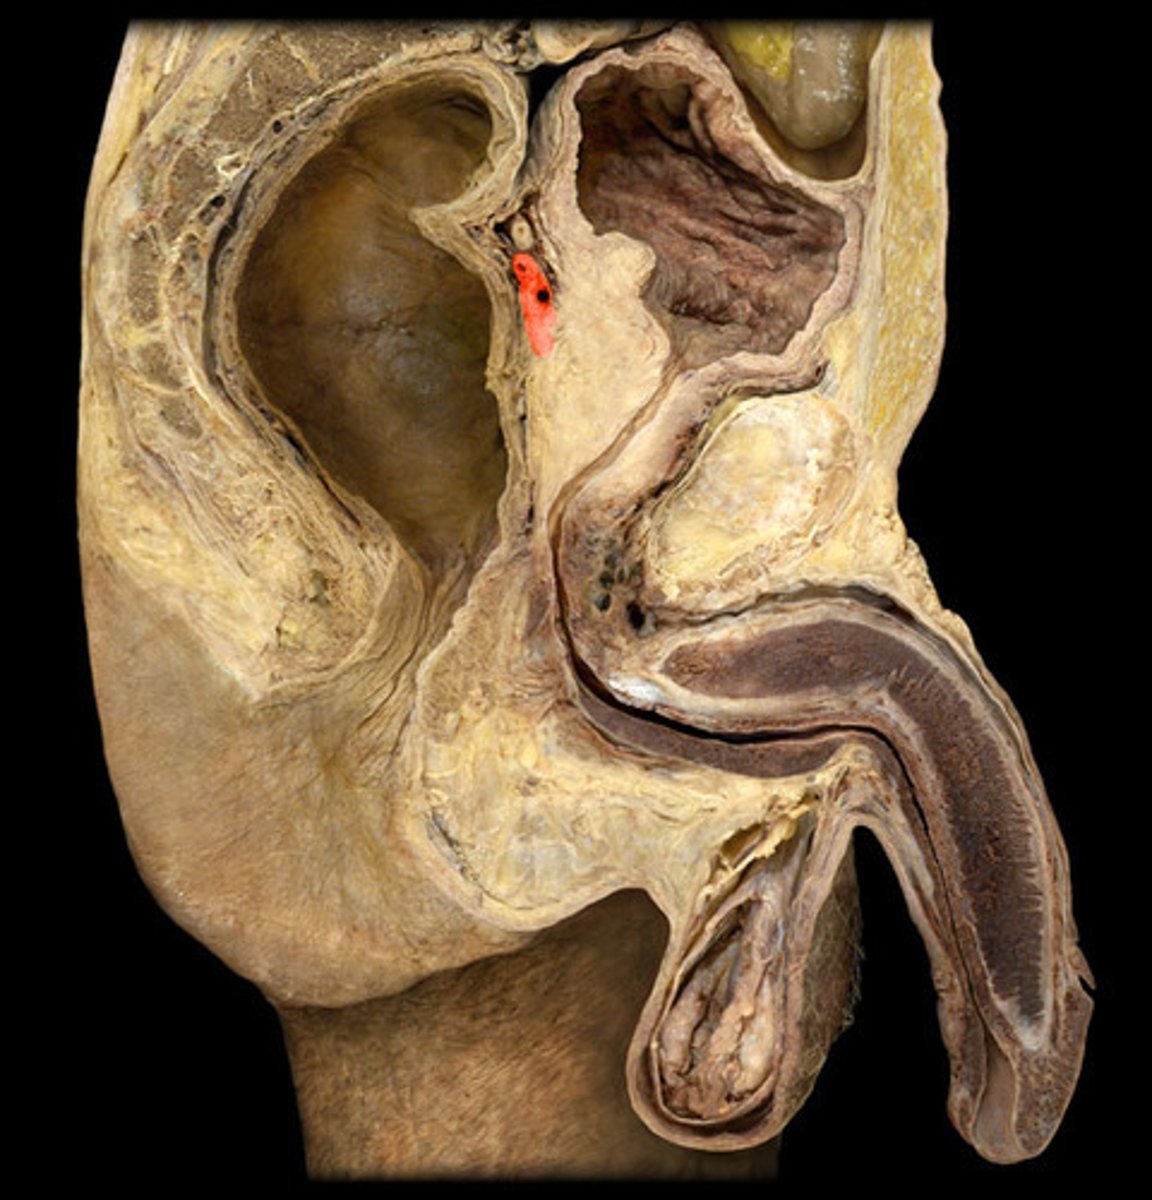

Vas Deferens

Seminal Vesicle

Prostate

Penis

Corpus Cavernosum

Glans Penis